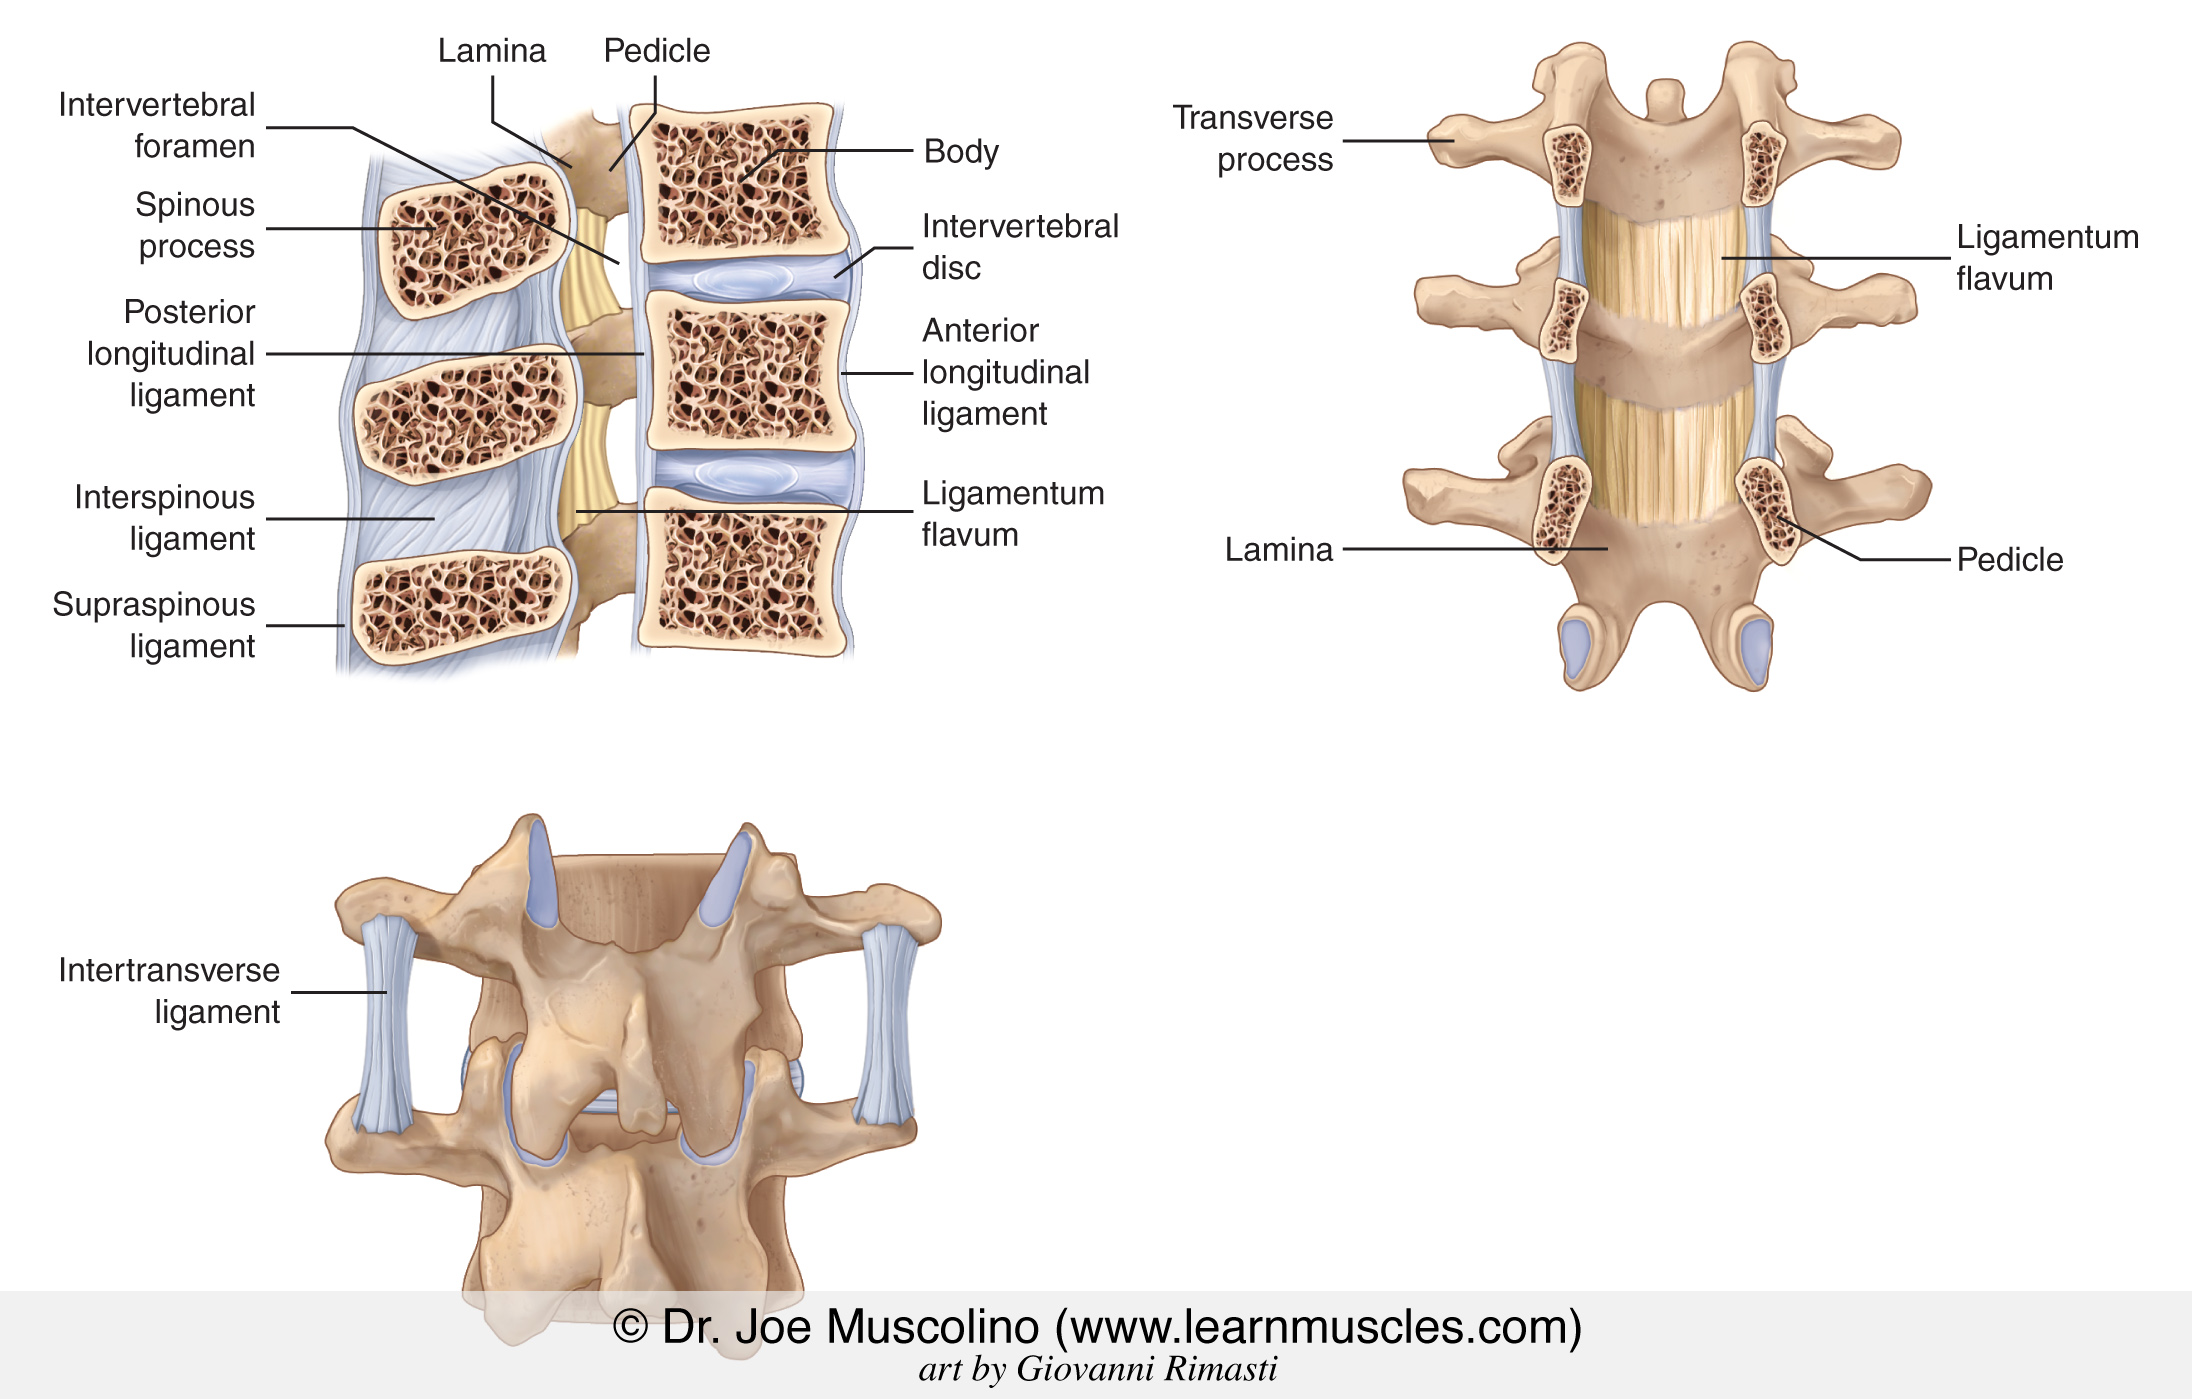

Pure Health - Anatomy 101 - Supraspinous ligament and interspinous ligament 📚 The supraspinous ligament and interspinous ligament work together to limit flexion of the spine by limiting separation of the spinous

DOCS - The interspinous ligament is located between the spinous processes of adjacent vertebrae in the spine. It extends from the base of one spinous process to the apex of the next,

Notes on Anatomy and Physiology: The Spinal Ligaments – Holding All The Parts Together |